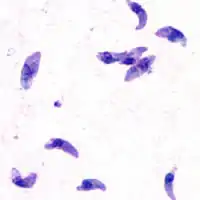

![]() T. gondii (тахізоїти) | ||||||||||||||||||

Всередині цих проміжних хазяїв паразит проникає в клітини, формуючи так звані міжклітинні паразитофорні вакуолі, що містять брадизоїти - форми паразита, які поволі відтворюють форми паразита[2]. Вакуолі формують тканинні цисти, в основному, в м'язах і в мозку. Оскільки паразит знаходиться усередині клітин, то імунна система хазяїна не може виявити ці цисти. Опірність до антибіотиків різна, але цисти дуже важко вивести з організму повністю. Усередині цих вакуолей t. gondii розмножується послідовністю поділу на дві частини доти, доки інфікована клітина врешті-решт не тріскається і тахізоїти не виходять назовні. Тахізоїти рухомі і розмножуються безстатевим способом, проводячи нових паразитів. На відміну від брадізоїтів, вільні тахизоїти легко усуваються імунною системою хазяїна, але при цьому можуть заразити клітини і сформувати брадізоїти, тим самим підтримуючи інфекцію.